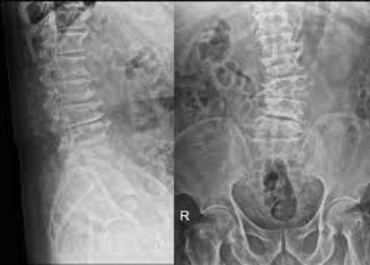

Case study on Herniated Disc

A herniated disc refers to a disc bulge at any of the spinal vertebrae. The vertebral disc in the spine has a unique structure and supports the cartilaginous joint. Usually, the spinal disc has a soft and jelly-like centre called the nucleus. This nucleus is present in a rubber-like structure called an annulus. A herniated disc occurs when the nucleus is pushed out to the annulus through the tear. It is also called a slipped disc or ruptured disc.